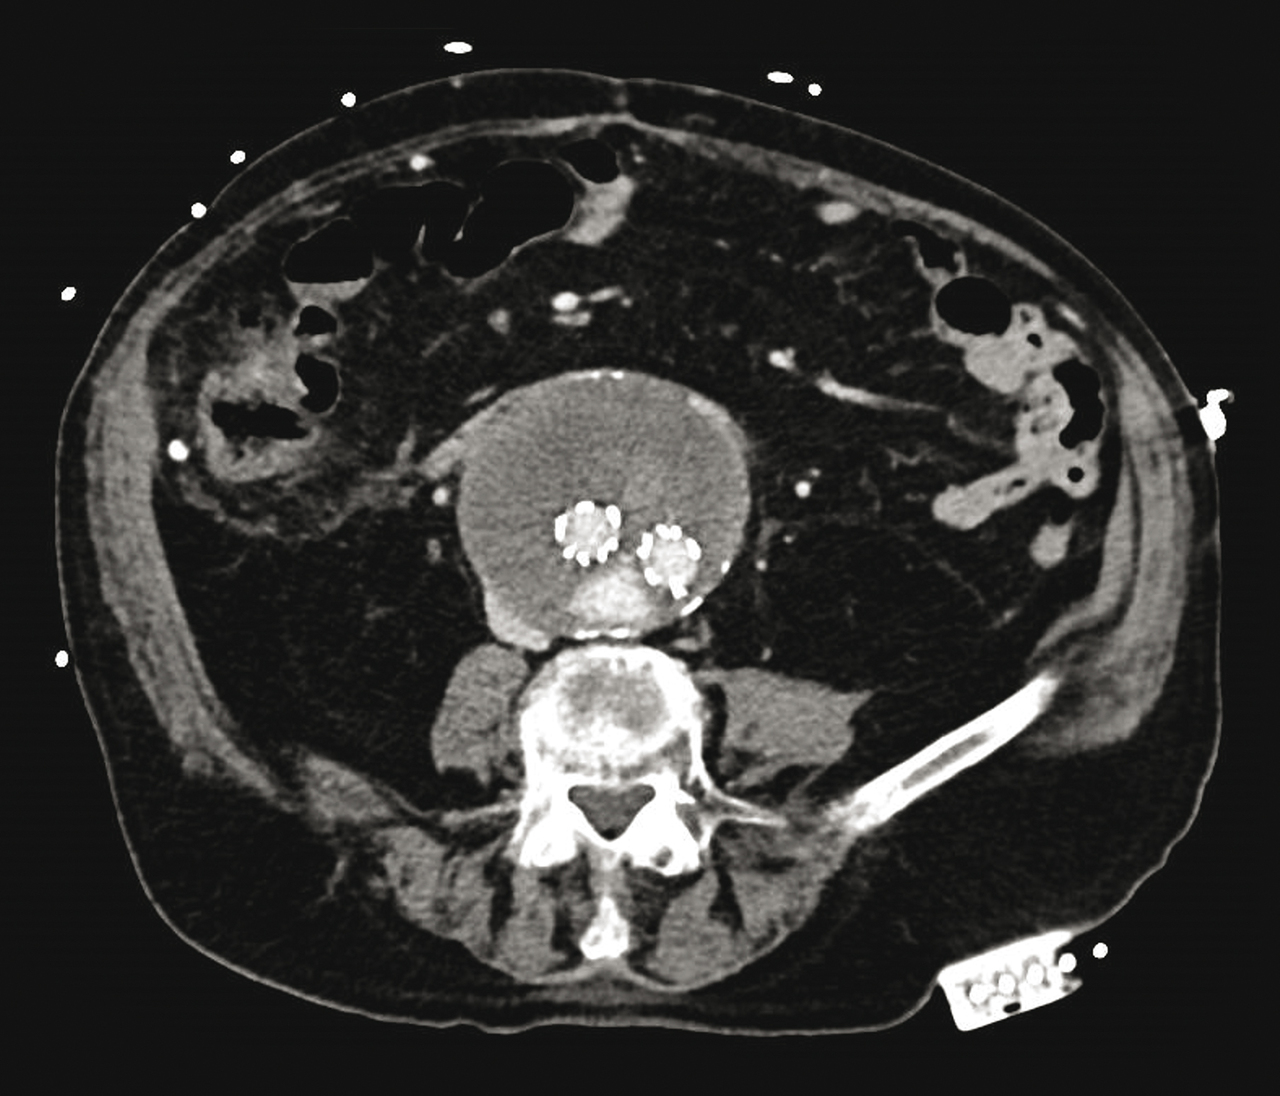

Homme de 92 ans hospitalisé pour douleurs abdominales et anémie.

Le traitement des anévrismes de l’aorte abdominale a été révolutionné par l’avènement des traitements endovasculaires, offrant des résultats à long terme comparables à ceux de la chirurgie conventionnelle. Cette endoprothèse, positionnée sous contrôle radiologique à l’aide d’un cathéter introduit à partir des artères fémorales, est positionnée au niveau de l’anévrisme. Une fois déployée, l’anévrisme est alors exclu de la circulation ; le sang s’écoulant, en aval de l’anévrisme, au travers de l’endoprothèse. Une surveillance est néanmoins nécessaire compte tenu du risque de survenue d’une fuite de sang entre la paroi aortique et l’endoprothèse (par une perte de l’intimité du contact) ou à partir d’une branche collatérale de l’aorte avec perfusion persistante de l’anévrisme. La surveillance après la mise en place d’une endoprothèse comprend, au moins un premier examen scanographique (angio-TDM dans la plupart des cas) postopératoire dans le mois qui suit, sauf contre-indication puis une surveillance régulière par échodoppler moyen et long terme.